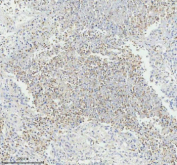

Immunohistochemical staining of GLIPR2 using anti-GLIPR2 antibody. GLIPR2 was detected in a paraffin-embedded section of human lung cancer tissue. Heat mediated antigen retrieval was performed in EDTA buffer (pH 8.0, epitope retrieval solution). The tissue section was blocked with 10% goat serum. The tissue section was then incubated with 2 ug/ml rabbit anti-GLIPR2 antibody overnight at 4oC. Peroxidase Conjugated Goat Anti-rabbit IgG was used as secondary antibody and incubated for 30 minutes at 37oC. The tissue section was developed using an HRP secondary and DAB substrate.